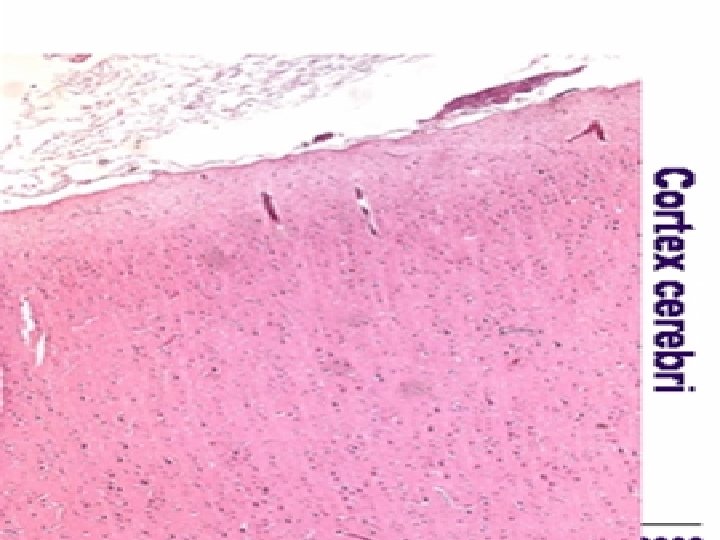

Cortex cerebri (HE) – lamina pyramidalis

Cortex cerebri (HE) – velké pyramidové buňky = multipolární neurony

Cortex cerebri (HE) – pyramidové buňky